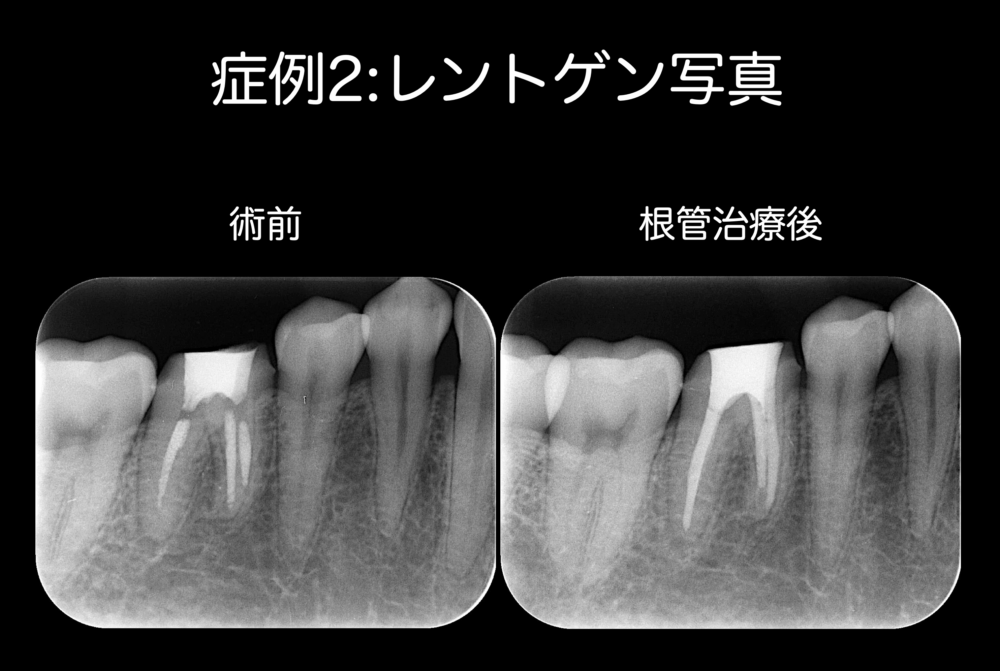

症例2:基本コンセプトを遵守している根管治療と外科的歯内療法で痛みが取れたケース

根管治療中から継続した痛みがあり、薬を詰めてはいる(根管充填)けれど、痛みが依然として残っていて外科的歯内療法で痛みが改善した症例です。

痛みの原因は、根の先の細菌を除去しきれなかったからではないか、と考えています。

根の先の部分は少しカーブしている状態で、このカーブの部分に器具を到達させることが難しく、機械的拡大ができず、細菌を除去できなかったから、痛みが残ってしまった、と考察しています。

左の写真の矢印の歯が患歯です。仮歯を外して根管治療を開始しましたら、右の写真の黄色い材料が見られました。この黄色い材料はよく使われる根管充填材料で、ビタペックスという暫間的に使用される材料です。一般的には乳歯の根管充填で使用されます。永久歯の根管充填にはガッタパーチャというゴムのような材料を使います。前医がビタペックスを使用した理由は、おそらくですが、根管治療中に痛みが取れていないので、症例1と同じような目的で、粗造な材料によって圧抜きしたかったのではないかと考察しています。しかし、基本コンセプトを遵守した根管治療における根管充填は、細菌を根管内に埋葬し、根の先に細菌を行かせないようにするために、根管を材料によって隙間なく詰めていきます。基本コンセプトを遵守した根管治療によって、根管を除菌し切っているにもかかわらず痛みが取れないのであれば、根管治療を修了させ、外科的歯内療法で痛みを取ります。

本症例は根尖部透過像を認めませんでしたが、患者さんは痛みを訴えていました。おそらく、根尖にレッジが形成されたため未形成部分ができ、痛みを発していたのではないかと考えています。実は、根管治療後外科的歯内療法を行って一度は痛みが改善されたものの、外科的歯内療法後1年ほど経過した際に、患者さんは痛みが再発した、とおっしゃっていたことがあり、以前と同様に根尖部透過像を認めてはいませんでしたが、再外科を行いました。再外科後2年が最長の観察期間時点において、痛みの再発はなく経過良好です。

要するに、痛みの原因は細菌を除去しきれなかったことにあって、詰める薬の種類によって痛みがなくなるわけではありません。